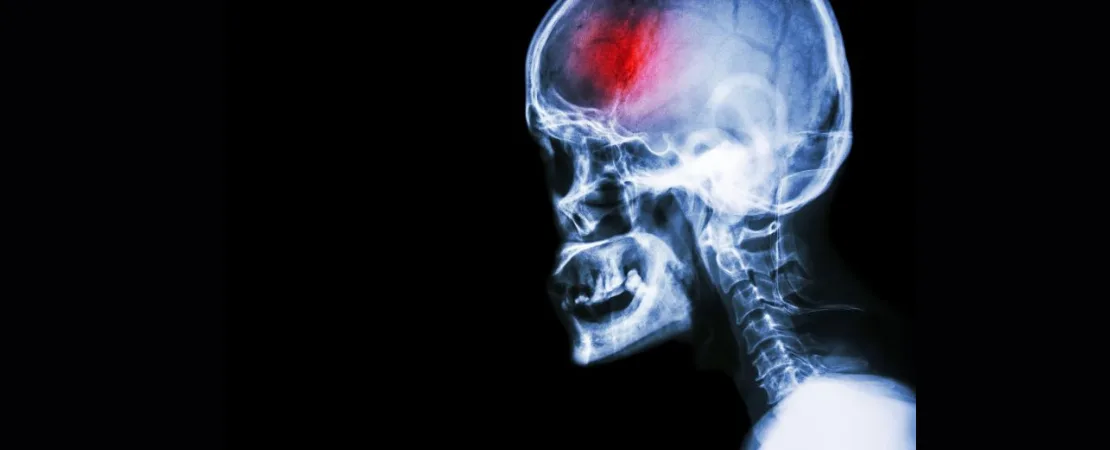

A stroke (previously known as a cerebrovascular accident) when there is a decreased flow of blood to the brain from either a blockage in the blood vessels that supply the brain (ischemic stroke), or a bleed from the blood vessels that supply the brain (hemorrhagic stroke). When the blood flow to the brain is blocked it prevents the brain from getting the needed oxygen and nutrients to function. Without oxygen the brain cells can be permanently damaged or die and the physical and mental functions related to that area of the brain will be affected. A stroke is a medical emergency and rapid treatment is crucial to decreasing the damage caused by a stroke.

Head X-rayA stroke is a serious medical emergency that requires immediate action in order to achieve the best eventual outcomes. Early medical intervention, as well as early, consistent and ongoing rehabilitation will positively affect your long term capabilities. Physiotherapy services at Physiocare Physiotherapy & Rehab Centre can assist you to recover from your stroke and regain your maximum potential.